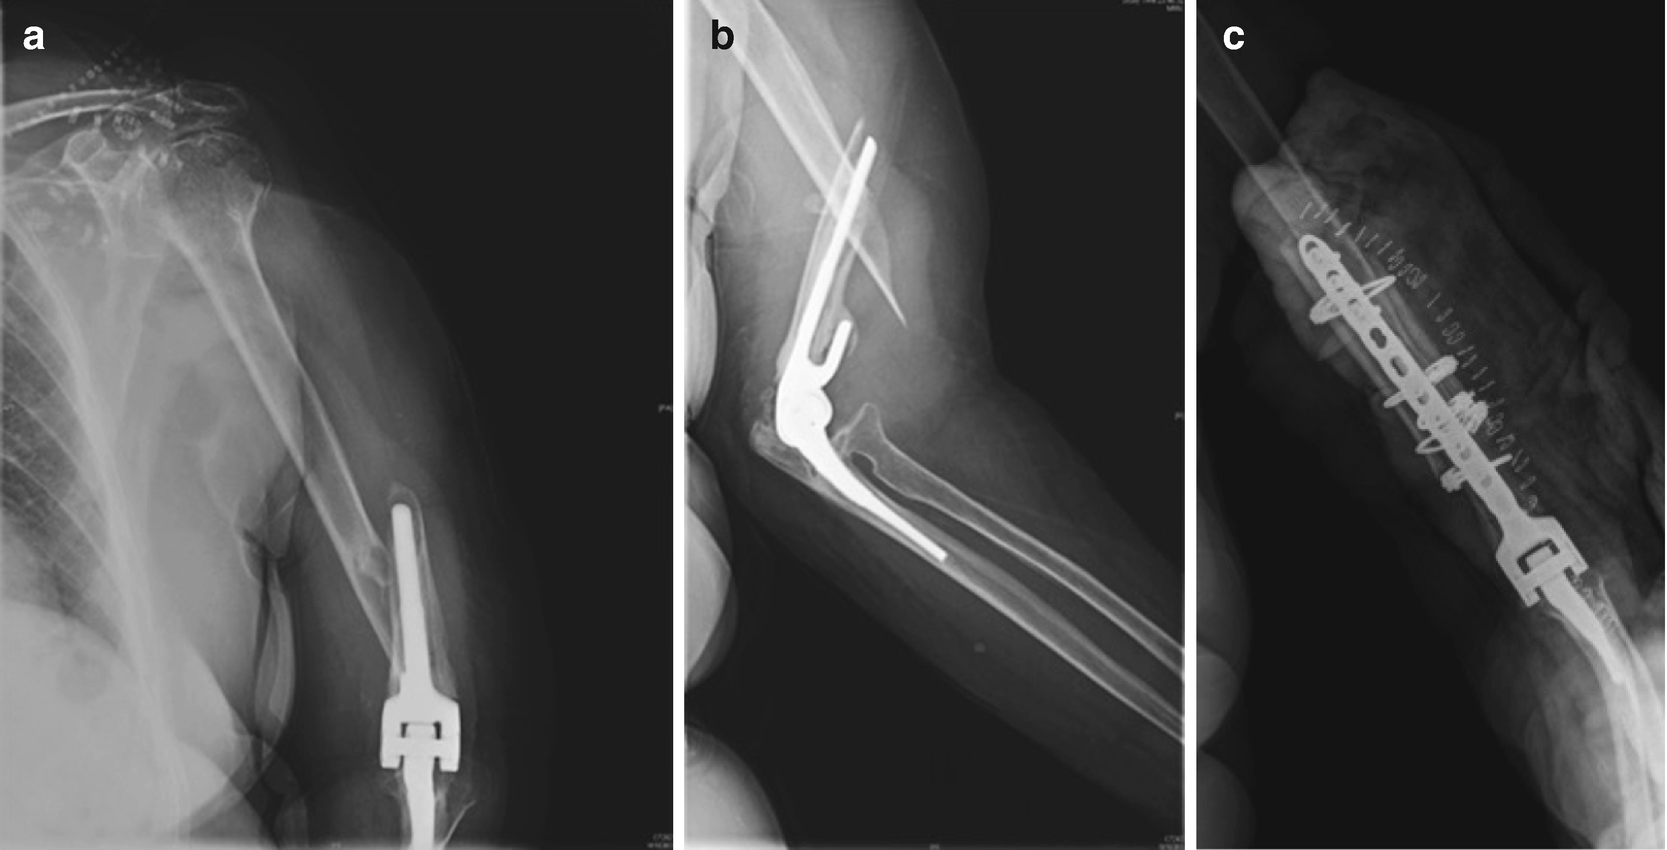

Revision Total Elbow Replacement:

Aseptic loosening, periprosthetic infection, or periprosthetic fracture with loose implants are the most prevalent reasons for revision total elbow arthroplasty.

In the case of periprosthetic fracture or implant loosening, radiographs are used to make the diagnosis. Inflammatory indicators and elbow aspiration can aid with periprosthetic infection diagnosis.

The kind of revision is determined by the cause of failure, the patient's age, and any comorbidities.